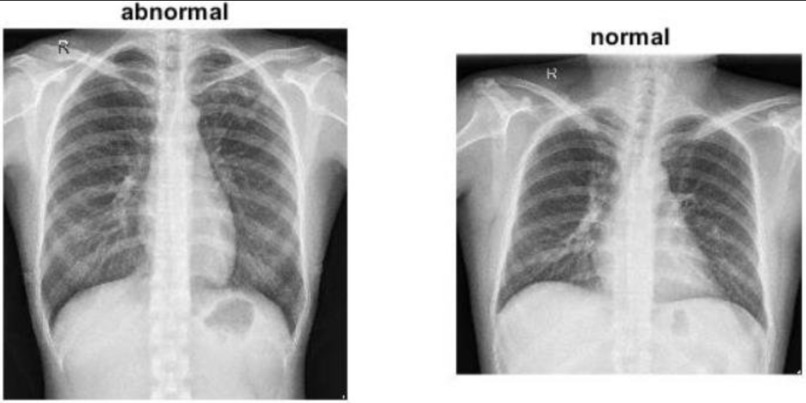

The inspiration for this project came from the urgent need for accessible, accurate, and fast medical diagnostics in healthcare, particularly in regions where expert radiologists are scarce. Chest X-rays are one of the most common imaging tests used to diagnose lung and heart diseases but interpreting them requires significant expertise and can be time-consuming.

The Chest-X-Ray-Medical-Diagnosis-with-Deep-Learning project uses deep learning techniques to automatically diagnose 14 different diseases from chest X-ray images. Here’s what the project does:

Automated Diagnosis: It leverages a trained deep learning model (typically a convolutional neural network) to analyze chest X-ray images and predict the presence of various pathologies such as pneumonia, fibrosis, edema, and others. Multi-label Classification: The model can simultaneously detect multiple diseases from a single X-ray image, reflecting real-world scenarios where patients may have more than one condition. Interpretability with Grad CAM: To enhance transparency, the project incorporates Grad CAM (Gradient-weighted Class Activation Mapping), which generates heatmaps to visually highlight the regions of the X-ray that influenced the model’s predictions. This helps users (doctors, radiologists, etc.) understand why the model made certain decisions. Aids Medical Professionals: The tool is intended as a diagnostic aid, supporting clinicians by providing fast second opinions and flagging potentially abnormal scans for further review. In summary: This project uses deep learning to automatically analyze chest X-rays, predict multiple diseases, and visually explain its decisions—potentially accelerating and supporting the medical diagnosis process.